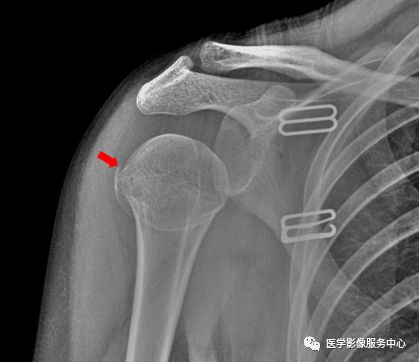

肩关节

右侧肱骨大结节骨皮质欠光整,见弧形透亮线。右侧肱骨大结节骨折。